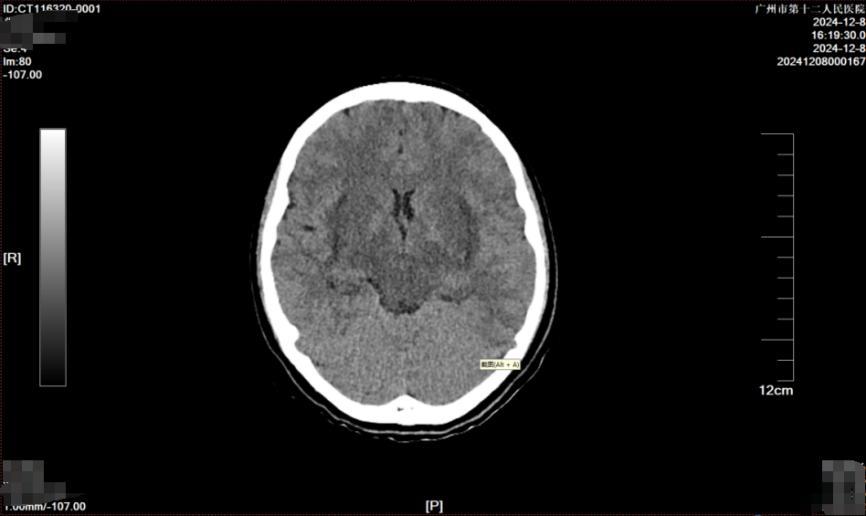

据了解,这是一名跨省转运患者,在抵达市十二医院黄埔院区前已在就近三甲医院接受了洗胃、血液净化等一系列紧急医疗干预措施。在5天治疗期间,小美病情仍在迅速恶化,甚至进展为多器官功能障碍,其中中毒性脑病尤为明显,出现了精神状态极度萎靡、无尿、肢体不自主震颤等症状。当地医生结合既往救治经验评估该病人生存机会渺茫,预计短期内死亡。

血肌酐水平高达760umol/L,转氨酶水平显著升高,提示肾、肝功能严重受损;肌红蛋白水平升高,表明存在横纹肌溶解症;血淀粉酶升高,并发了中毒相关胰腺炎……根据各项检查结果及患者临床表现,重症医学科团队快速敲定了个体化救治方案,其中包括精细化的液体管理、毒物监测指导下的个体化血液净化方案、肺保护下的脑保护措施等,力求在最短时间内稳定患者的生命体征。

2小时后,小美血压、心率等生命迹象逐步稳定,但全身凝血功能障碍、多器官功能衰竭、中毒性脑病等危重状态,仍然提示病情依然不容乐观。张瑞昌表示:“当时患者还出现了凝血功能异常延长,全身多处渗血,不单是皮肤黏膜出血,且口咽和气道出血比较明显,这也给气管插管增加了不少难度。”